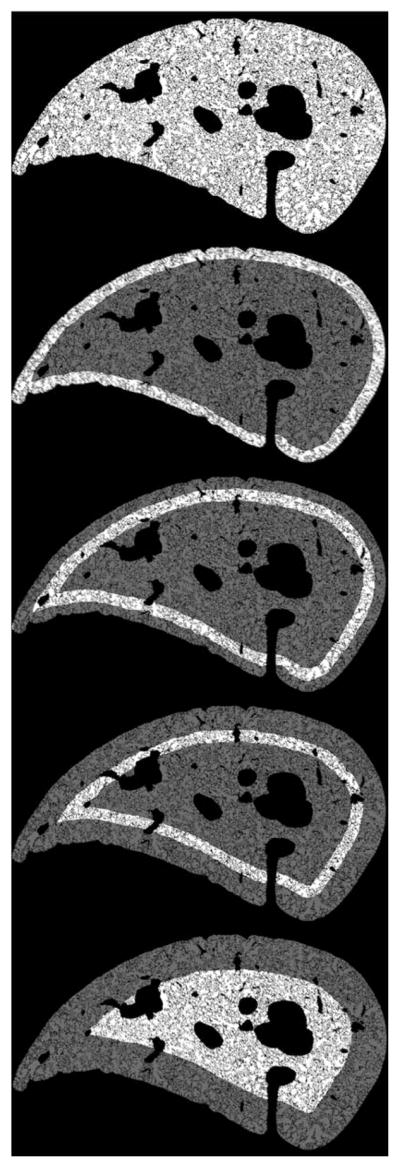

FIGURE 2.

Concentric rings and sections independently analyzed. The bright highlighted regions are the areas analyzed. The thickness of each white ring shown is 300 μm. For the quantitative analysis, the outermost ring shown was divided in half, but this is not shown here for clarity.